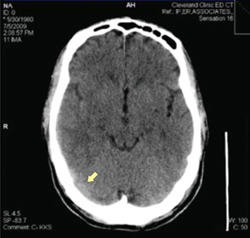

• Don’t order neuroimaging routinely; it is not necessary for diagnosing concussion. Neuroimaging is important, however, for patients who exhibit prolonged unconsciousness, focal neurologic deficits, or worsening symptoms (A).

When a CT is required